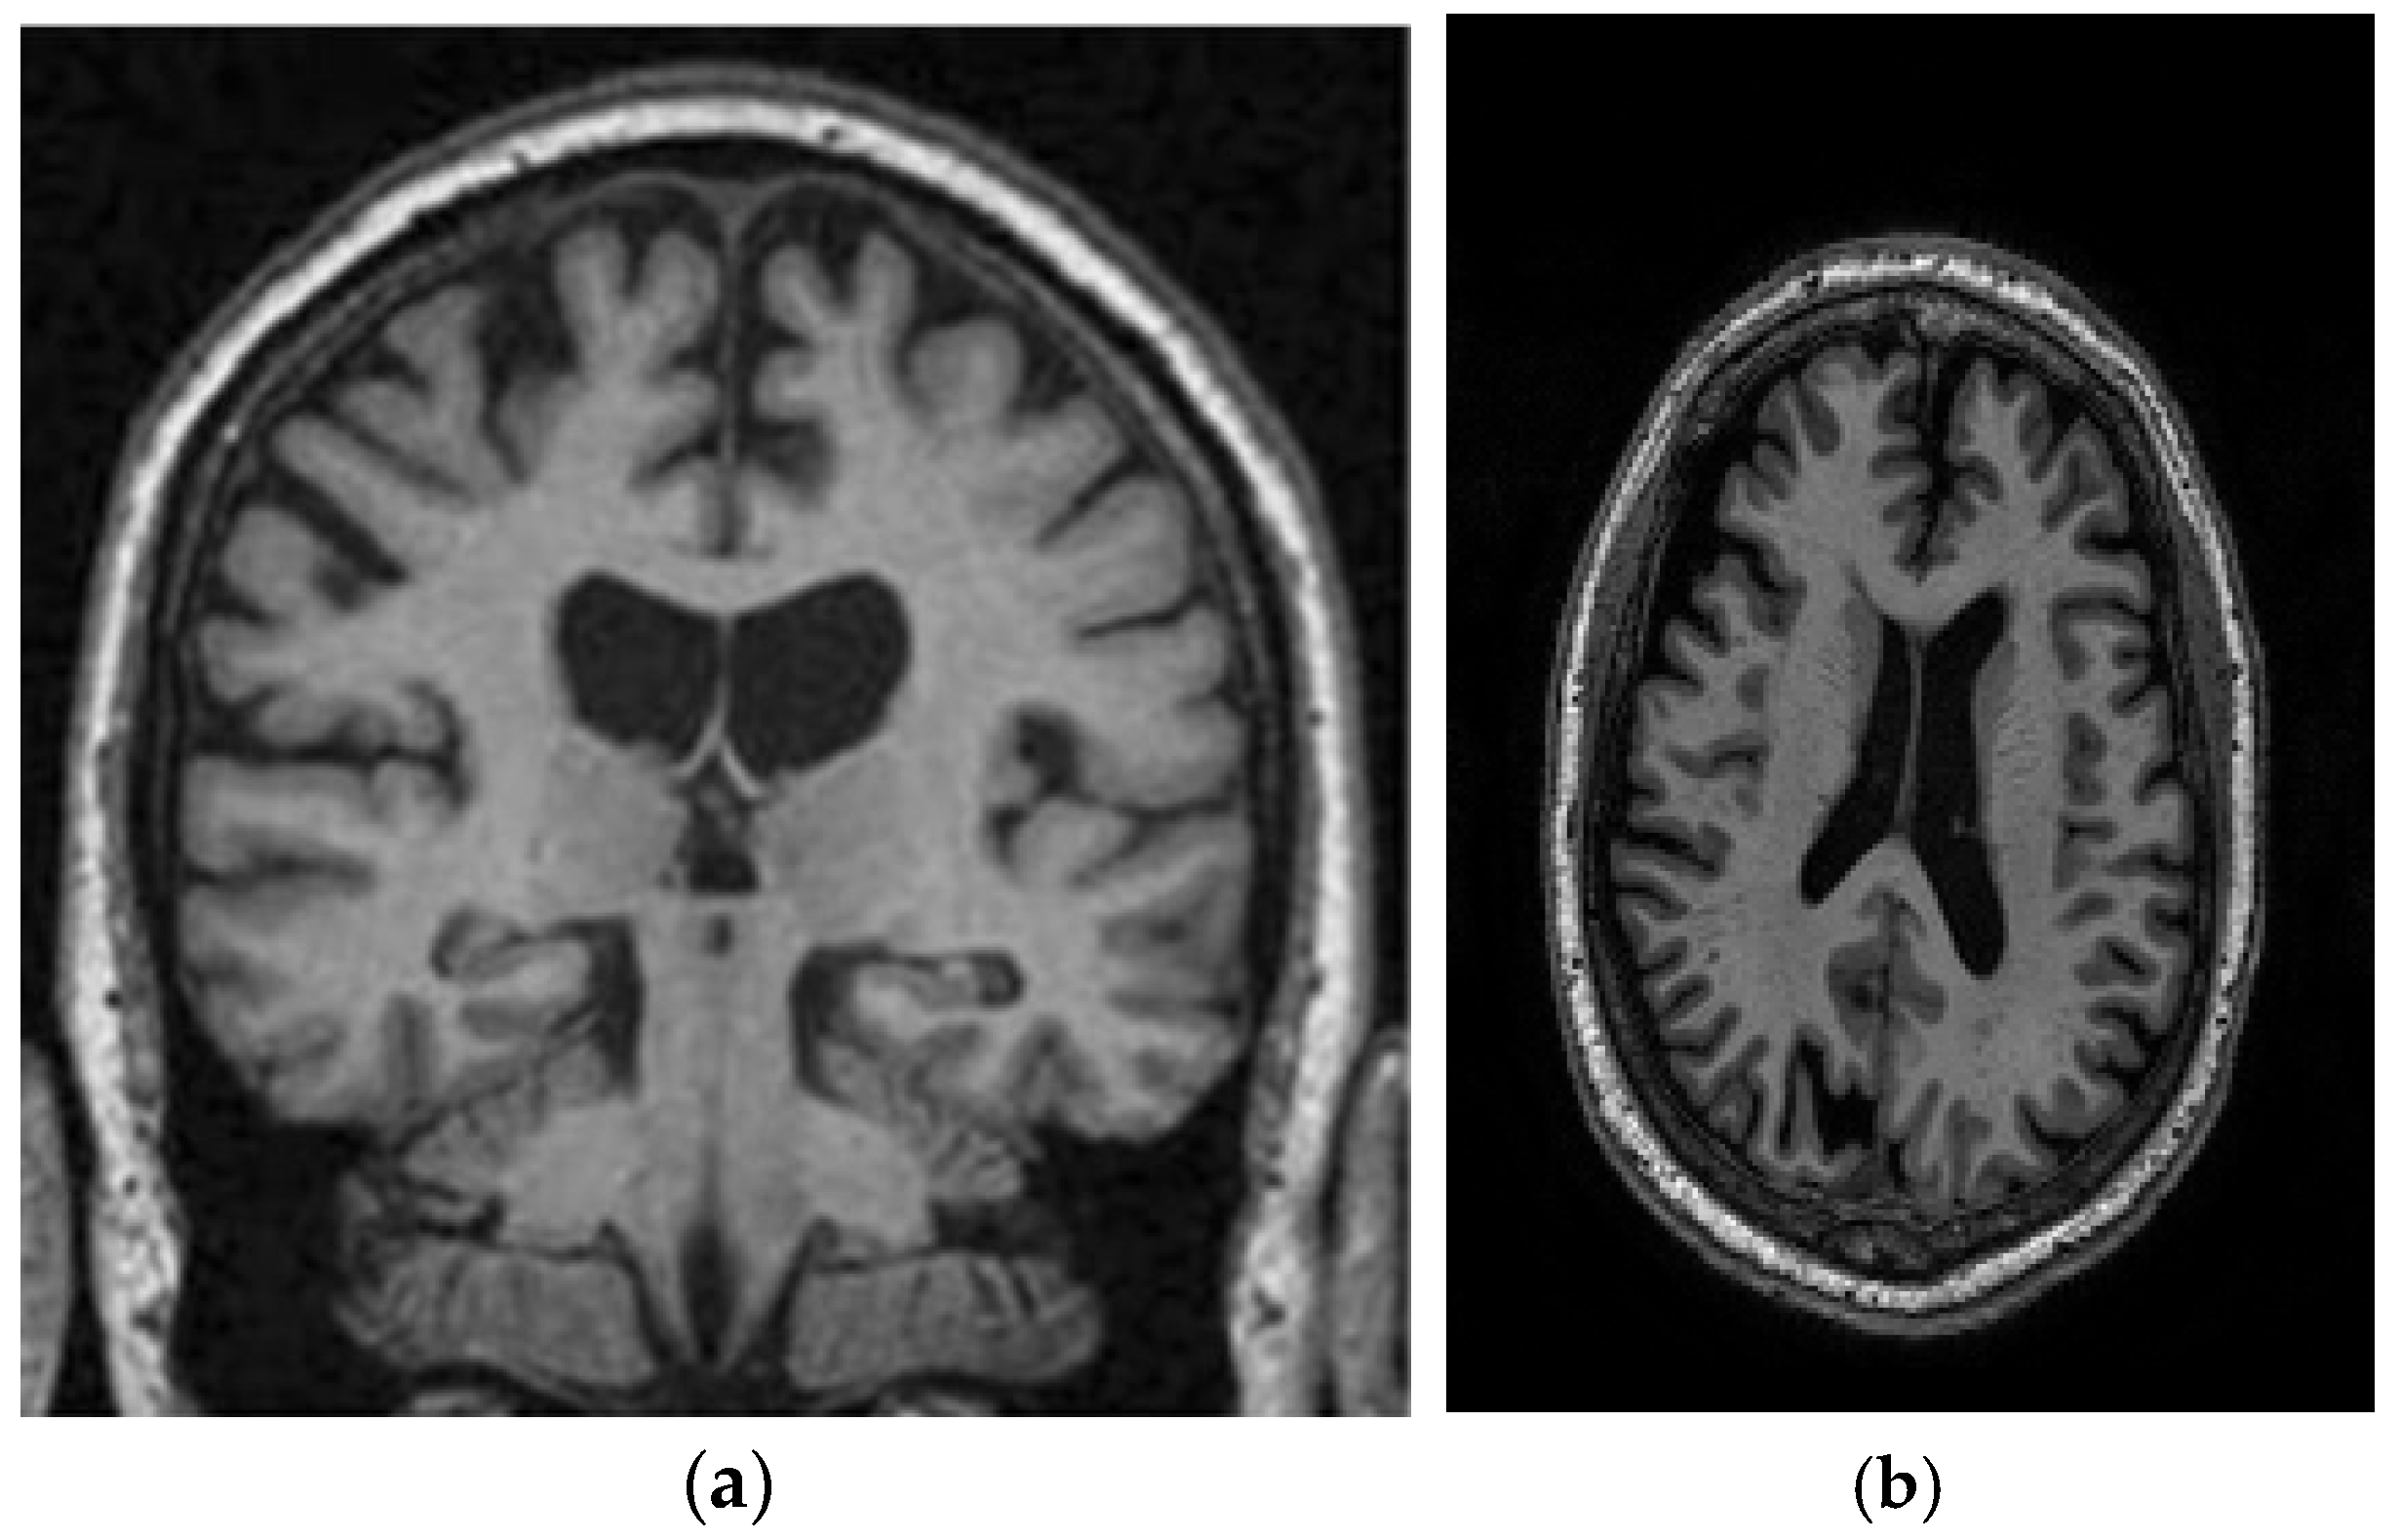

This study utilizes two distinct datasets, ADNI and MIRIAD, to investigate Alzheimer’s disease, ensuring a diverse range of demographics and imaging modalities. The ADNI dataset, which tracks the early stages of Alzheimer’s, consists of MRI scans, specifically 128 sagittal slices per scan, each formatted as a 256 × 256 matrix. It includes a total of 741 participants, with 314 images from Alzheimer’s patients and 427 from normal controls. The participants represent a wide variety of ages, genders, and ethnic backgrounds, ensuring that the model is robust and can perform well across different populations. The MIRIAD dataset also focuses on Alzheimer’s, containing MRI brain scans from 46 Alzheimer’s patients and 23 normal controls, with follow-up scans taken at intervals ranging from 2 weeks to 2 years [44,45]. Both datasets are sourced from various institutions, introducing variability in the acquisition conditions, which further enhances the model’s robustness and its ability to generalize to real-world scenarios. The inclusion of different ethnic backgrounds, as well as varying patient ages and scan intervals, ensures that the model is adaptable to diverse clinical environments. Figure 8 shows examples of benign and malignant images from these datasets. Table 1 summarizes the key settings and configurations used in the experiments to analyze Alzheimer’s disease using HHO and CNN-based approaches.

Figure 8.

Two sample images from the ADNI and MIRIAD datasets: (a) MIRIAD dataset [46]; (b) slices from the ADNI Dataset [47].